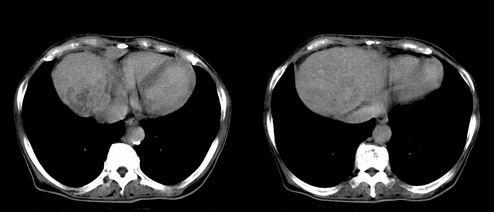

患者 女性 58岁,家族有乙肝病史,(并姊妹中已有3人确诊肝癌,真是不幸!乙肝病毒真是害死人!)近期明显消瘦,乏力,右上腹疼痛.行ct结果非常典型,请诸位老师会诊!

图片非常漂亮!肝内病灶符合较典型肝癌的强化方式,速升速降,其内可见坏死,腹膜后示肿大淋巴结融合成团,包绕腹主动脉、腹腔干动脉、肠系膜动脉。右肾小囊性病灶,未见明显强化。

肝癌伴门静脉及下腔静脉癌栓形成,腹膜后淋巴结转移.

肝癌伴腹膜后淋巴结转移,肝硬化伴脾大,好像没有发现门静脉及下腔静脉瘤栓形成.

1、肝右叶肝癌,后腹膜淋巴结转移(包绕腹腔干及肠系膜上动脉,推压门静脉、下腔静脉及胰头)

2、肝硬化、脾肿大

3、右肾小囊肿

2、肝癌,动静脉瘘(动脉期门静脉内造影剂进入)

3、后腹膜淋巴结转移,下腔静脉推移